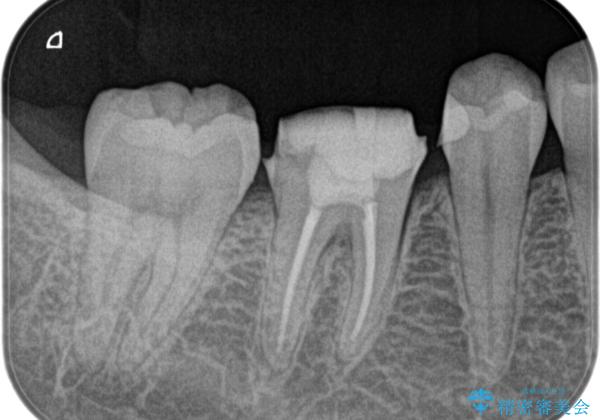

【根管治療】噛んだら痛い。ズキズキ痛い

- 4日前から噛んだ時に痛むことを主訴に来院された患者様です。

歯髄壊死/症候性根尖性歯周炎の診断のもと、根管治療を行なっております。

- 精密根管治療(イニシャルケース,大臼歯):122,000円、ファイバーコア:22,000円費用は治療当時の料金となります